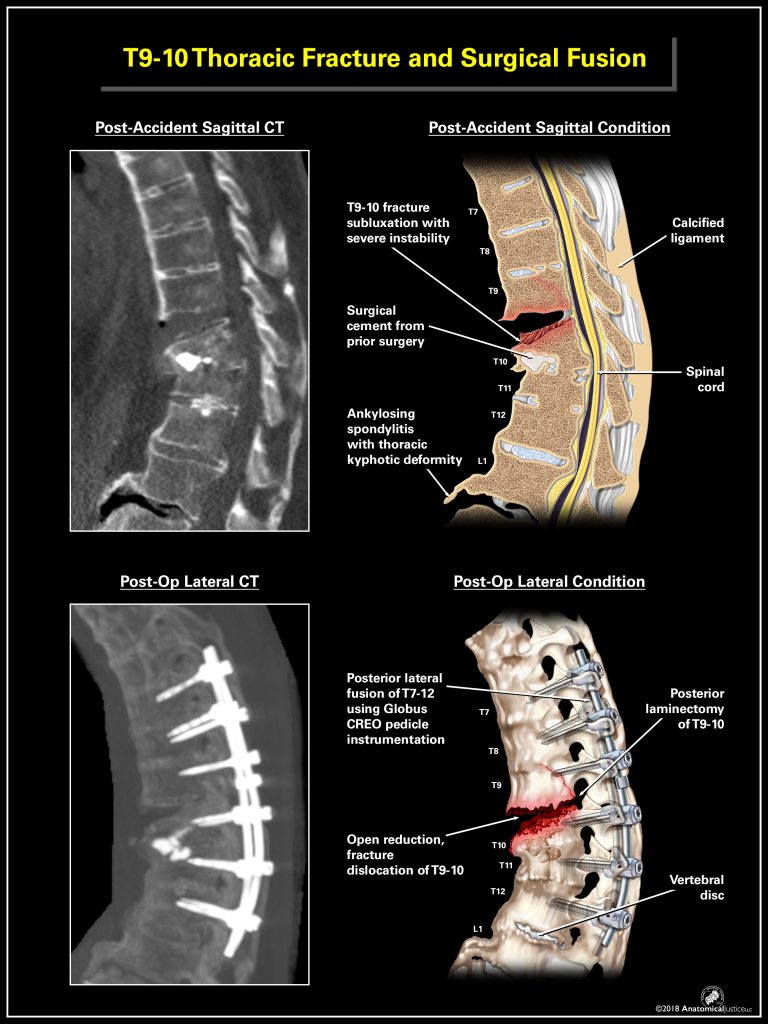

Radiological Illustration

Utilizing our creative services to simplify diagnostic anatomy allows your patrons to understand the complexity of the human body. Our staff can render medical imaging from any source, including X-rays, Fluoroscopy, Computed Tomography (CT), Ultrasound and Magnetic Resonance Imaging (MRI). Once visually translated, apply these films to all your presentation needs.